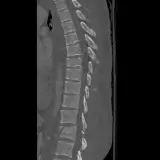

Over 2,100 interactive radiology cases, curated by radiologists for your level of training. Scroll, window, and view cases full screen โ€” just like on PACS. Click linked findings in each writeup to jump straight to them on the image. Cases include sample reports, a focused discussion section, original illustrations, and videos.

Casi completamente interattivi con gli strumenti che ti aspetti su un PACS: scroll, windowing, zoom, pan, misurazioni, ROI e modalitร  a schermo intero.

Annotazioni dettagliate evidenziano i reperti chiave direttamente sui casi. Clicca sui reperti collegati nella descrizione del caso per saltare alla loro esatta posizione sullo scan.